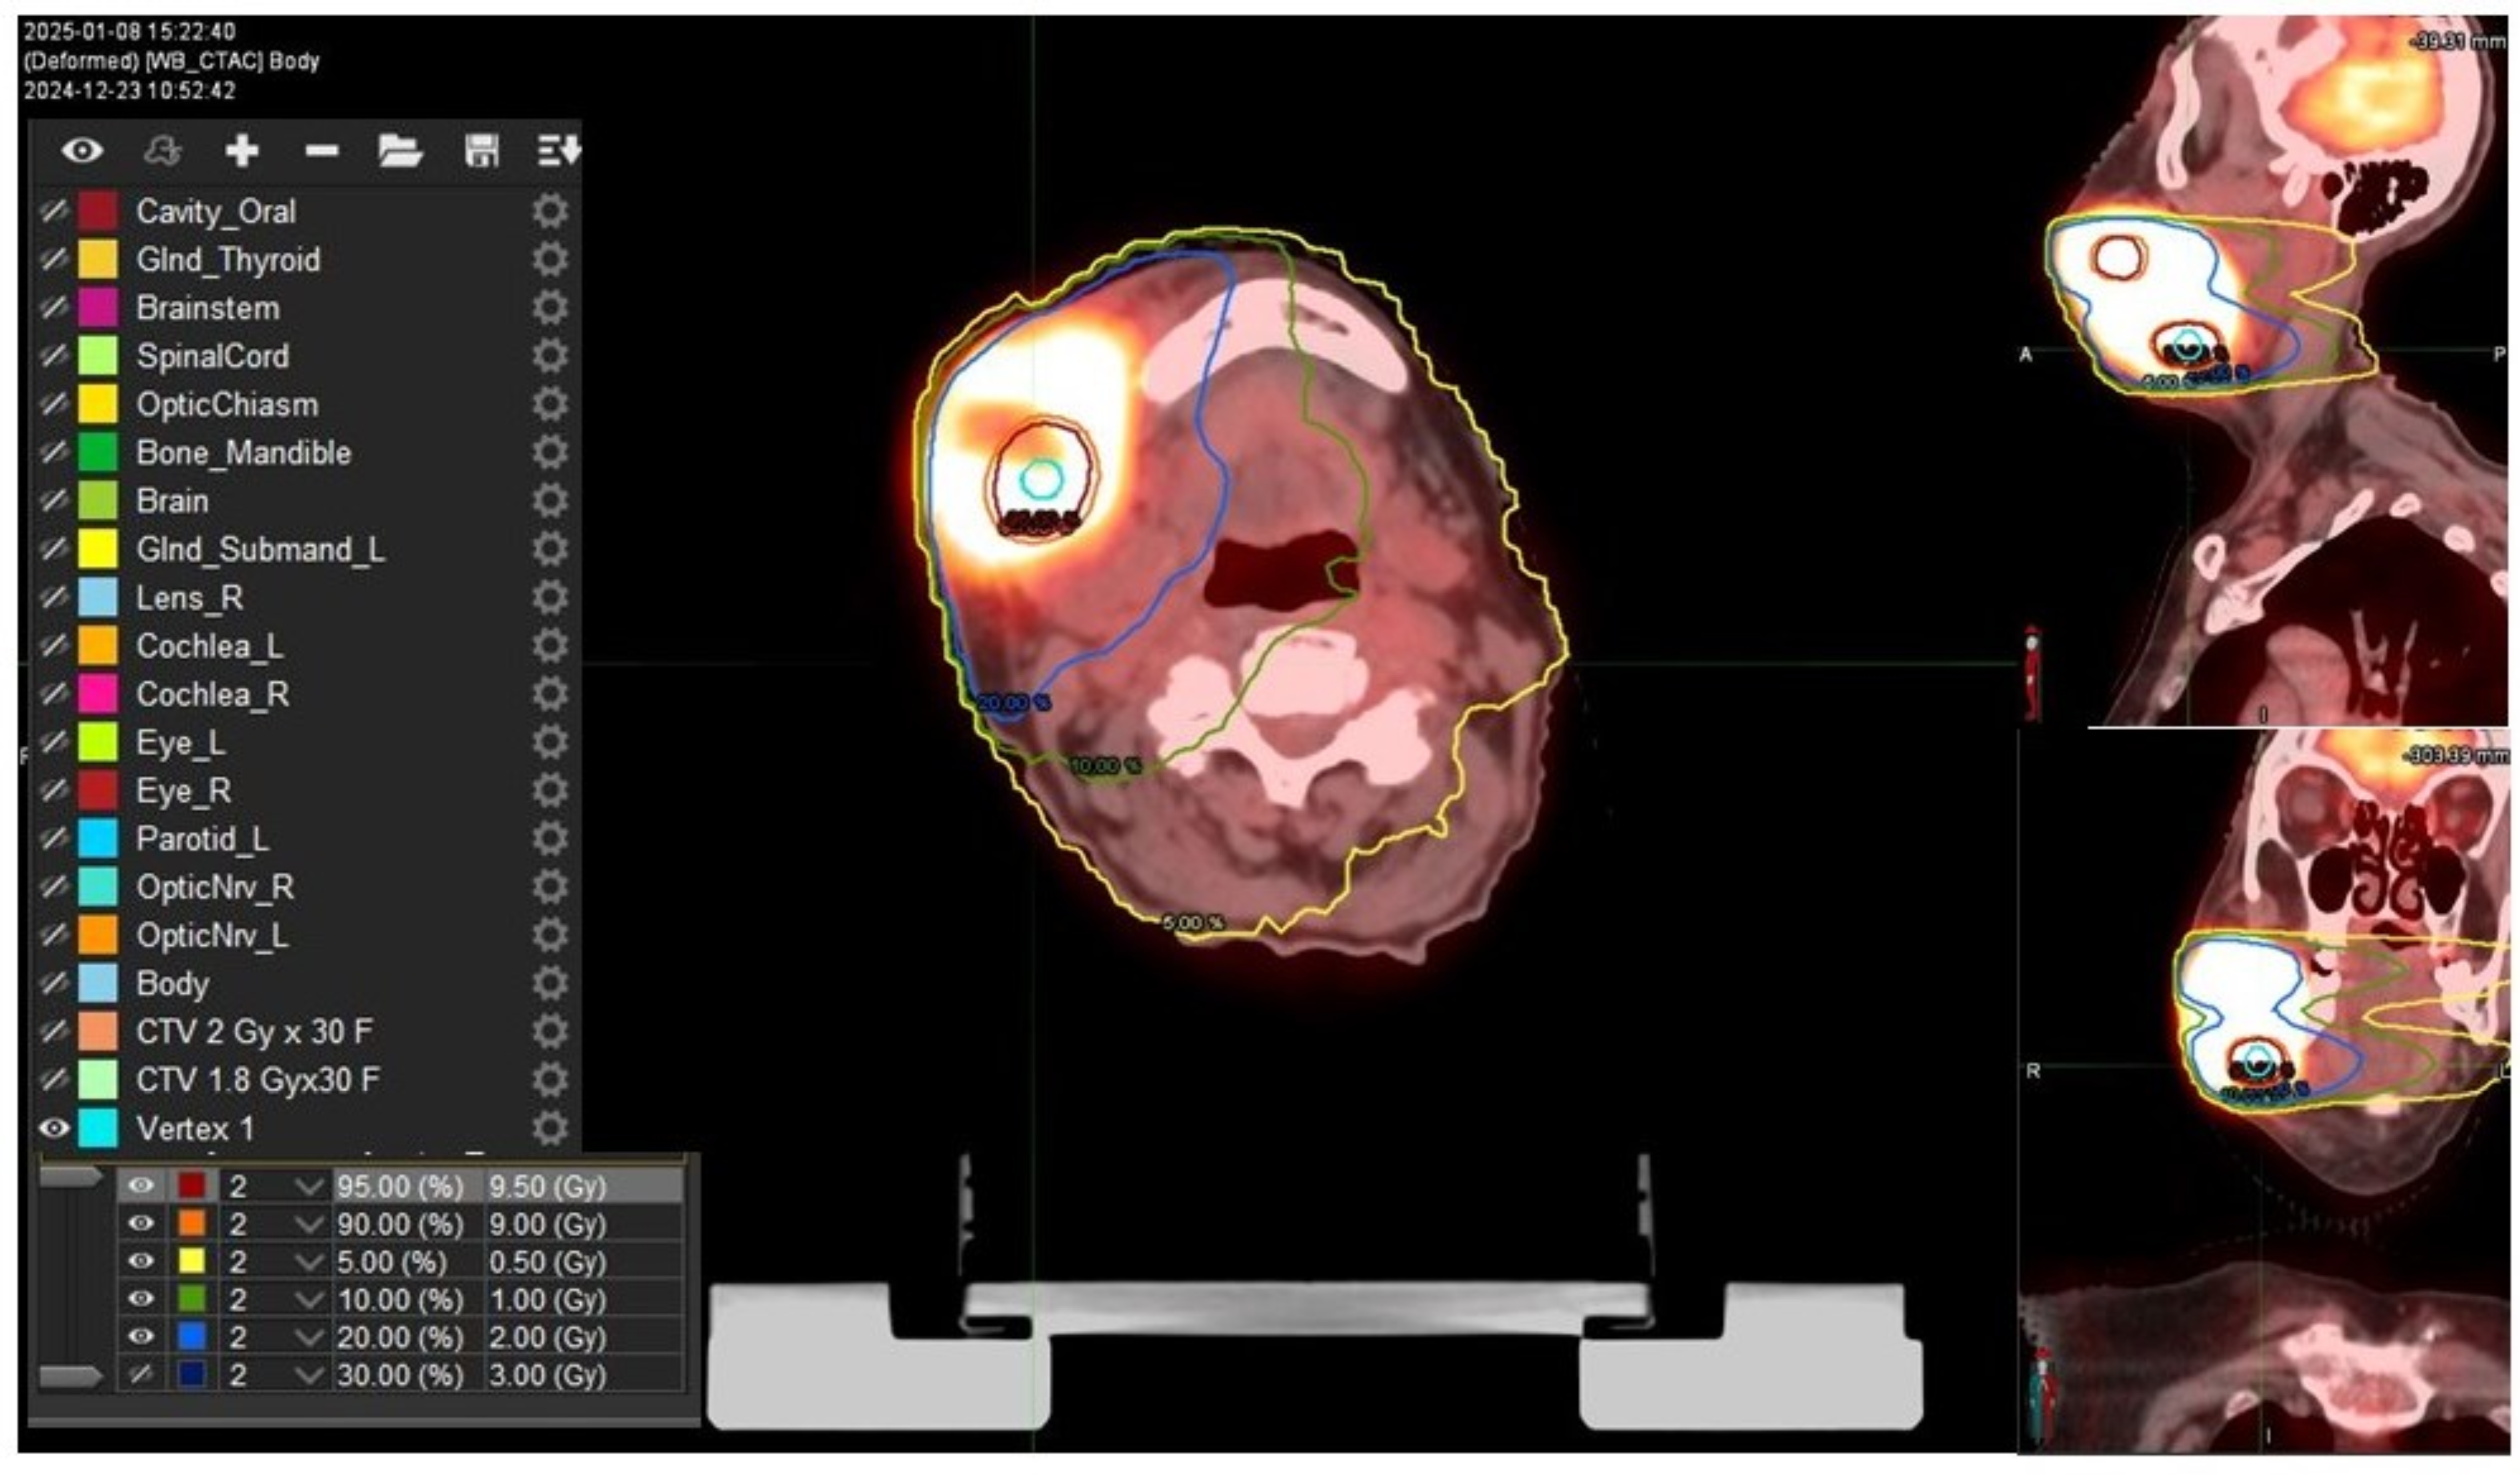

2. Case Presentation